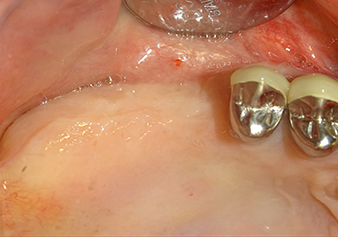

The Schneiderian membrane is stretched 1.5-2 mm above the bony access

Fig.4: Intermediate check: The bone height above the maxillary sinus floor is approx. 4 mm palatal and buccal; the Schneiderian membrane is stretched 1.5-2 mm above the bony access.